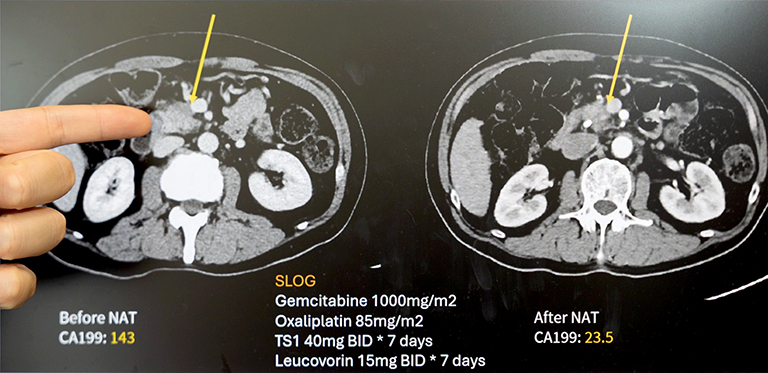

62歲的王先生出現體重減輕與黃疸症狀,經檢查確診為胰臟癌。影像顯示腫瘤已侵犯門靜脈,屬於「邊界可切除」階段。過去此類病人往往難以直接接受手術,預後也較差。經成大醫院外科團隊多專科評估後,王先生接受「術前化學治療(Neoadjuvant Chemotherapy, NAC)」合併「擴大胰臟切除手術(Extended Pancreatectomy, EP)」。歷經四個月化療,腫瘤明顯縮小,順利完成合併血管重建的胰十二指腸切除術。術後追蹤兩年,病人恢復良好、生活如常。

▲六旬翁確診胰臟癌接受「術前化學治療合併擴大胰臟切除手術」。術後追蹤兩年,病人恢復良好、生活如常。